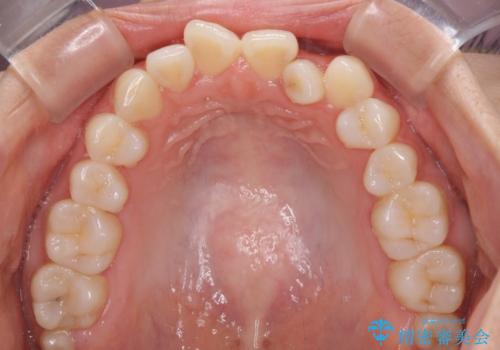

- 前歯のデコボコを気にして来院された患者様です。

前歯のデコボコはもちろん気になるところですが、舌の突出癖により上下の前歯に大きな隙間がある状態でした。

舌の突出癖の影響もあり、非抜歯矯正で治療開始したものの口元が突出し、唇が閉じにくくなってしまったため、途中で第一小臼歯4本を抜歯ししました。

口元の突出感のない、すっきりとした仕上がりとなりました。